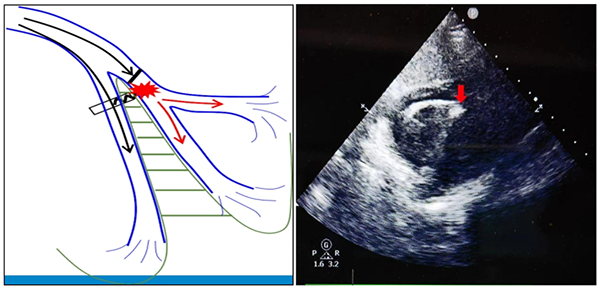

左束支区域起搏是2017年中国黄伟剑等人在国际上首次报道:一名心力衰竭合并完全性左束支传导阻滞的扩张型心肌病患者左室电极植入困难,尝试做希氏束起搏以纠正左束支阻滞,但是阈值很高难以接受。为了跨越阻滞部位,得到更低的起搏阈值,将电极更远更深地穿越并植入室间隔内,到达左室间隔面心内膜下,由于此处有丰富的浦肯野纤维网,结果意外获得右束支阻滞的起搏图形、左束支电位和比希氏束起搏更好的起搏参数。随访3年,参数非常稳定,心力衰竭显著改善,心脏完全缩至正常,手术效果超出预期。该意外发现的创新性技术操作通过模拟心脏的自然电生理路径,有效改善心室收缩同步性,提高心脏的泵血效率。左束支区域起搏技术目前在成人缓慢型心律失常患者中得到推广,并在国内外研究中验证了其可行性、稳定性、有效性及安全性,在多方面已经显示出其超越希氏束起搏的优势,包括生理性起搏位点比希氏束起搏操作更简单,使左室收缩同步化,单根电极即可纠正左束支传导阻滞,能跨越病变等,甚至可能成为心脏再同步化治疗(CRT)的替代方案。

自2020年以来,中国仅有清华大学第一附属医院、上海儿童医学中心、北京安贞医院等少数医院小儿心脏科开始开展此先进手术技术,标志着中国在儿童心脏病治疗技术方面的进步和创新。2023年2月,省立医院儿科主任、小儿心脏科主任韩波教授带领团队,成功为一名13岁三度房室传导阻滞伴左室扩大的患者植入了山东省首例LBBAP模式的双腔抗核磁心脏永久起搏器,手术顺利成功,各项指标恢复良好。截至目前,科室已完成LBBAP手术9例,其中最小1例患儿年龄3岁,所有病例均顺利完成,无手术并发症发生。团队通过对儿童左束支区域起搏技术的初步探索发现,左束支区域起搏术后心电图 QRS 波时限均保持较窄,起搏参数良好稳定,患儿左心室内径较比术前明显缩小且心功能均保持良好。结合国内外少量医学中心的研究报告,目前左束支区域起搏技术在儿童中的运用是安全可行的。